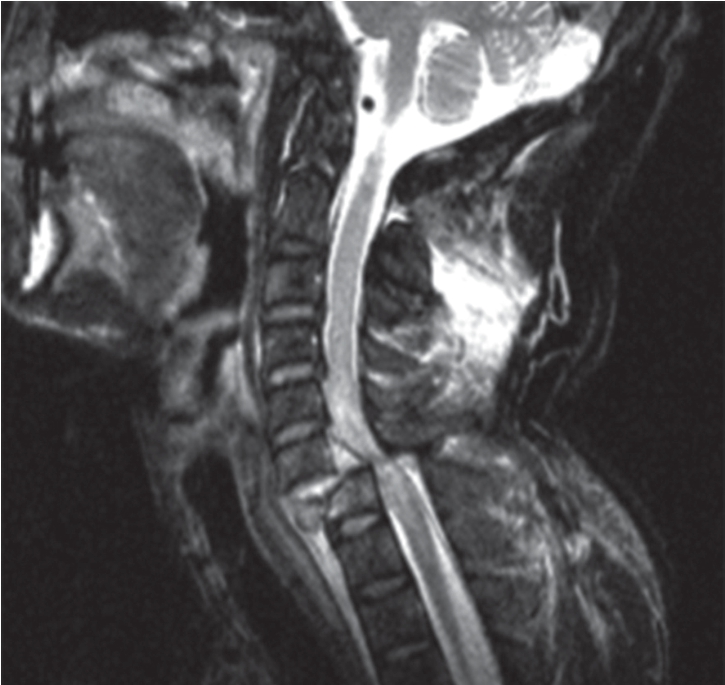

骨折并脱位指骨折伴有椎体脱位、上下关节突绞锁。游离骨折片可突入椎管。严重者可发生脊椎后突成角、侧移。骨折并脱位主要表现是损伤椎体压缩呈楔形或轻度压缩变形,椎体明显脱位,常超出下一椎体上面的一半以上,严重者脱位椎体完全超出下一椎体的前方;下一椎体也可出现前缘骨折,骨折碎块随上一椎体前移。常伴有附件如关节突、椎弓等骨折,小关节常半脱位及交锁;严重者可伴有脊髓损伤(图7-2-17)。

图7-2-17 MRI示第7颈椎骨折并脱位